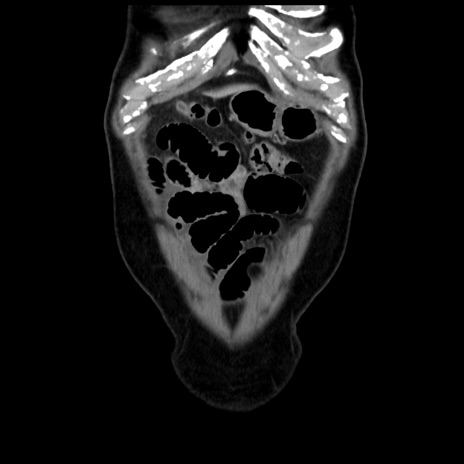

症例16(冠状断像)

【症例】 70歳代男性

【主訴】 腹痛、嘔吐

【現病歴】 約1ヶ月前より間欠的に腹痛と嘔吐あり、当院消化器内科を受診したところCTで多発する肝臓のLDAを指摘され、精査中であった。以降は消化器症状は安定していたが、2日前より嘔気と腹痛があり、同日より排便・排ガスが消失した。改善認めず、 本日、救急外来を受診した。

【身体所見】意識清明・会話良好、BT 36.3℃、BP 127/80mmHg、 P 80bpm、腹部:膨満あり、平坦・軟、上腹部正中および下腹部正中に圧痛あり、反跳痛なし、筋性防御なし。

【データ】WBC 7200、CRP 0.77